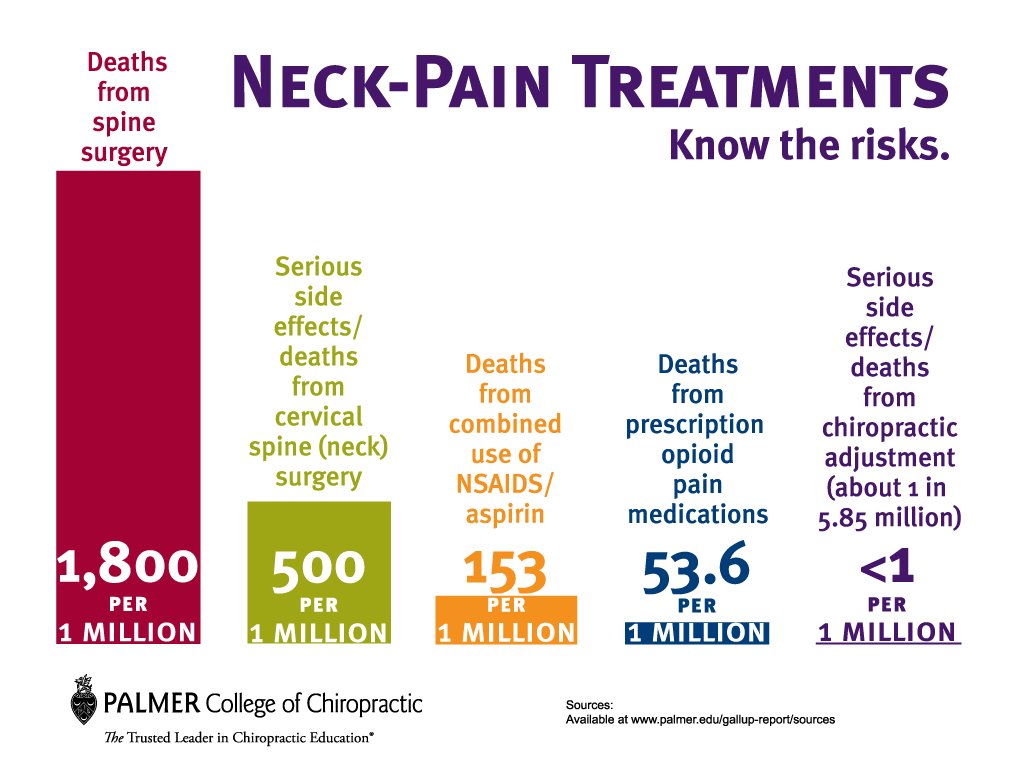

カイロプラクティックの安全性について

カイロプラクティックの安全性について